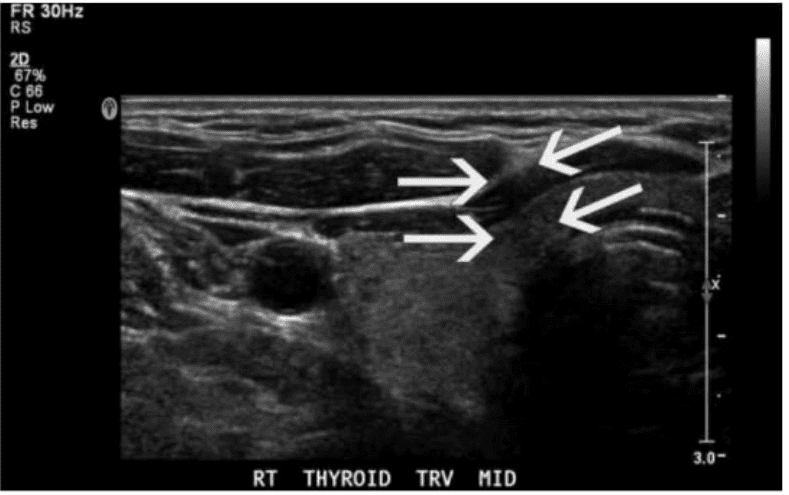

Which type of artifact is indicated by the arrows on this image?

Where in the neck are most thyroid cancer recurrences found?